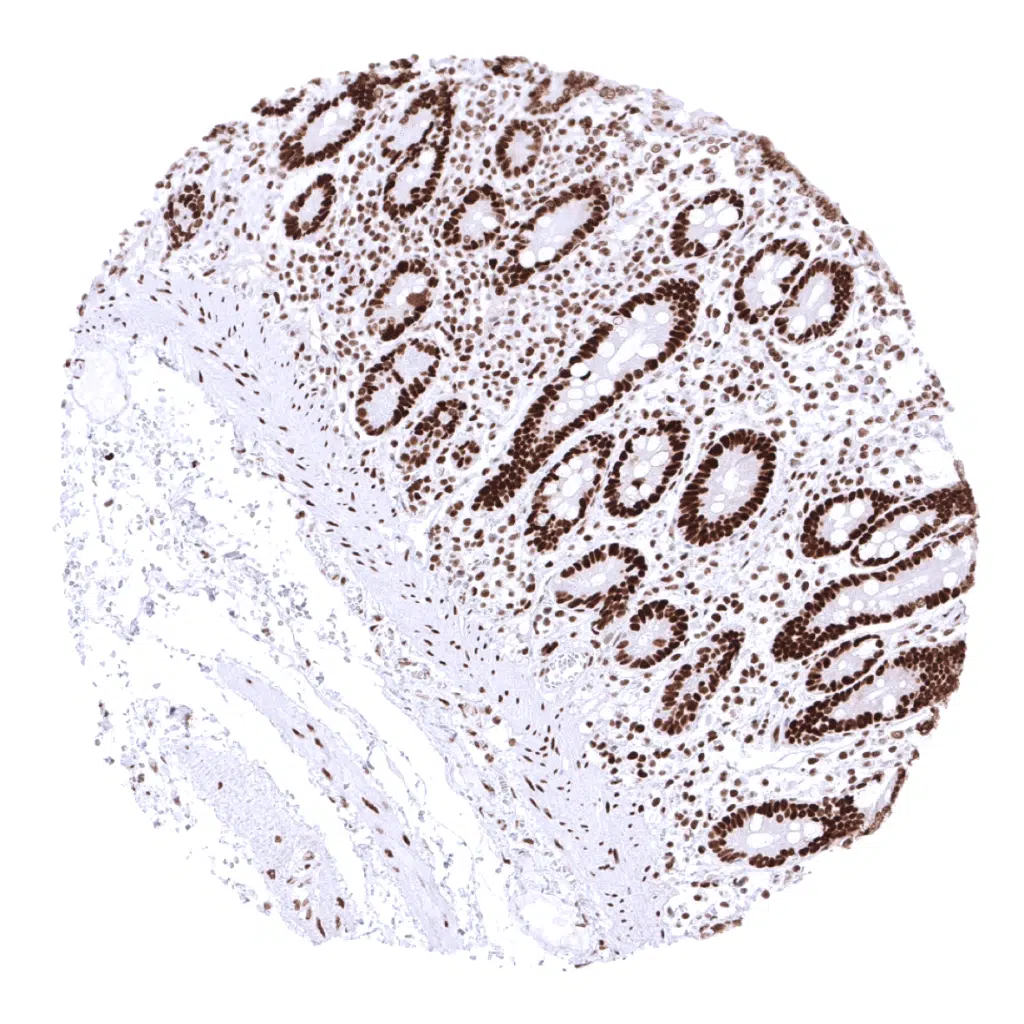

MSH2 antibody [MSVA-902M] HistoMAX

Colon, mucosa – In the colon epithelium, the MSH2 staining intensity decreases from the bottom to the top of the crypts.

Rectum, mucosa – In the colon (and rectum) epithelium, the MSH2 staining intensity decreases from the bottom to the top of the crypts.